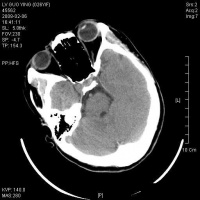

脑干含有大部分的脑神经核(除了嗅神经视神经),全身感觉、运动传导束,及呼吸循环中枢,脑干网状结构参与和维持意识清醒。故损伤后出现…… 1.意识障碍 原发性脑干损伤病人,伤后常立即发生昏迷,轻者对痛刺激可有反应,重者昏迷程度深,一切反射消失。如有昏迷

脑干损伤CT图

持续时间较长,很少出现中间清醒或中间好转期,应想到合并颅内血肿或其他原因导致的继发性脑干损伤。

8.CT扫描 是目前辅助诊断颅脑损伤的重要依据。能显示颅骨骨折、脑挫裂伤、颅内血肿、蛛网膜下腔出血、脑室出血、气颅、脑水肿或脑肿胀、脑池和脑室受压移位变形、中线结构移位等。病情变化时应行CT复查。

9.MRI 急性颅脑损伤患者通常不作MRI检查。但对病情稳定的弥漫性轴索损伤、大脑半球底部、脑干、局灶性挫裂伤灶和小出血灶、等密度亚急性颅内血肿等,MRI常优于CT扫描。

2.颅脑CT、MRI扫描 原发性脑干损伤表现为脑干肿大,有点片状密度增高区,脚间池桥池四叠体池及第四脑室受压或闭塞。继发性脑疝的脑干损伤除显示继发性病变的征象外,还可见脑干受压扭曲向对侧移位,MRI可显示脑干内小出血灶与挫裂伤,由于不受骨性伪影影响,显示较CT清楚。